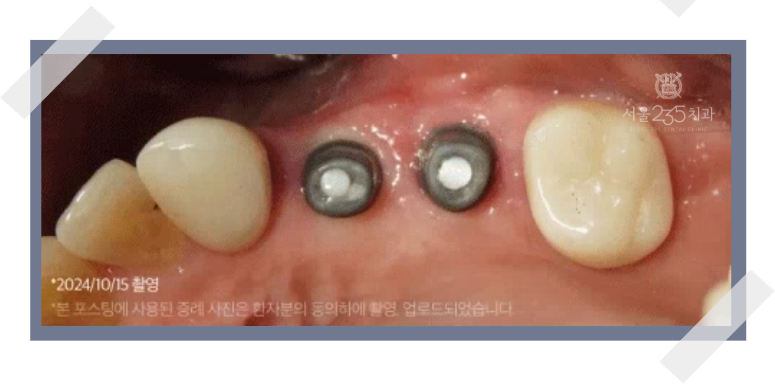

완성도 높은 남양주 임플란트를 위해서는

뼈이식을 통해 단단한 경조직을 재건한 후,

위축된 잇몸(연조직)까지 복원하는 과정이 필요합니다.

근단변위판막술, 구강전정성형술과 같은 잇몸 수술을 통해

임플란트 주위에 충분한 양의 단단한 잇몸(각화치은)을 만들어주면,

장기적으로 안정적인 임플란트 사용이 가능해집니다.